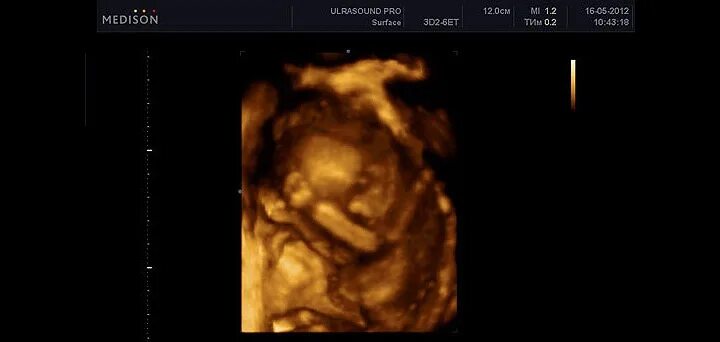

16 неделя можно ли узнать пол ребенка